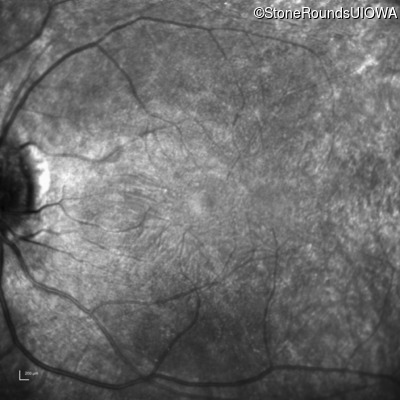

Infrared Fundus Photograph - Right - 20/25 +2

Exemplar